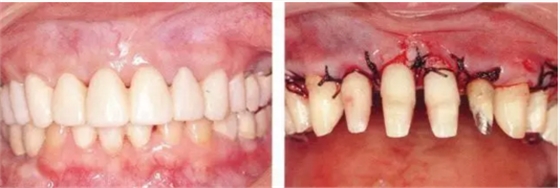

病例9

對患有重度牙周疾病的患者,采取包括了正畸、牙周、種植、修復(fù)在內(nèi)的綜合性治療的病例

2222222222.png

▲圖19-1

40歲,女性。來院主訴為牙齦出血,牙體晃動?;颊卟晃鼰?,因此沒有全身性問題。有明顯的牙周炎,發(fā)生了牙體移動,前牙區(qū)前突。下頜右側(cè)磨牙缺失,醫(yī)生認(rèn)為有必要進(jìn)行包括牙周修復(fù)、正畸治療、種植治療等在內(nèi)的綜合性治療。

33.png

▲圖19-8,9

▲圖19-8 佩戴臨時修復(fù)體。即使在這個狀態(tài)下,依然有牙周袋殘留。

▲圖19-9 完成牙周外科治療后的狀態(tài)。